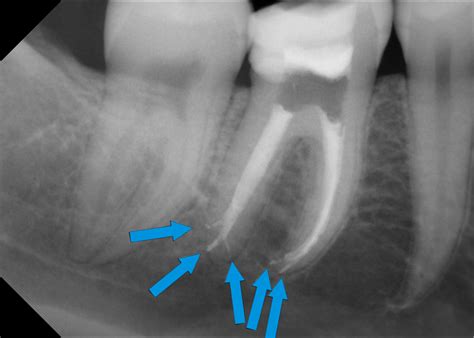

Röntgenbilder sind entscheidend, um den Zustand des Knochens um die Wurzelspitze zu beurteilen und Entzündungen (wie Granulome oder apikale Ostitis) zu erkennen. Sie zeigen auch, ob eine Wurzelbehandlung dringend notwendig ist, um grösseren Schaden wie z.B. eine Fistel oder Eiterbeule (Abszess) zu verhindern. In komplexen Fällen, wenn normale Röntgenaufnahmen unauffällig sind, kann eine 3D-Volumentomographie (DVT) notwendig sein, um versteckte Entzündungsherde oder nicht gefüllte Wurzelkanäle aufzudecken.

Überfüllung der Wurzelkanäle

Die Wurzelkanäle werden über die Wurzelspitze hinaus aufbereitet oder gefüllt (Überfüllung). Dabei gelangt Zement (Sealer) oder Guttapercha in den Knochen und kann dort Probleme wie akute oder chronische Fremdkörper-Entzündungen auslösen. Besonders kritisch ist es, wenn Wurzelfüllmaterial in die Kieferhöhle oder den Nervkanal im Unterkiefer gelangt. Manchmal ist eine chirurgische Entfernung der Wurzelspitze (Wurzelspitzenresektion) erforderlich, um den Fremdkörper zu entfernen.